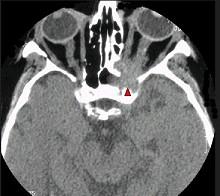

问题 下列关于眶蜂窝织炎(如图)正确的是 ( )

选项 A、瞳孔异常主要是因睫状神经结受累 B、是一种特异性炎症 C、最常见由于面部疖肿引起 D、分为眶隔前或后两种 E、可引起海绵窦血栓静脉炎

答案 E